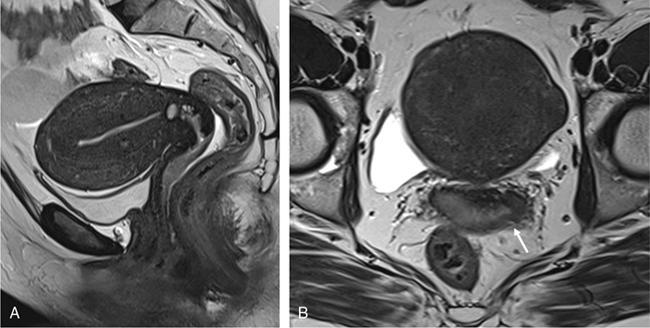

VAGINAL CYSTS Sumeena The vagina is a fibromuscular sheath. Vagina extends from uterus to the vulvar vestibule. The vagina is located in the middle compartment of the pelvis and it is related anteriorly to bladder and urethra, posteriorly to lower rectum and anal canal. The length of vagina ranges from 4 to 12 cm. The posterior wall of vagina is longer and it ends in posterior fornix; the anterior wall is shorter and ends in the anterior fornix. The wall of vagina is composed of three layers: (a) The mucosa consists of nonkeratinized stratified squamous epithelium without glands and its hormone sensitive layer; (b) the muscularis made up of connective tissues and smooth muscle; and (c) the adventitia, which is fascia that connects the vagina to the surrounding pelvic structures and maintains support. The prevalence of vaginal cysts is estimated to be less than 1%. They typically present in the age of 30–40s. Their origin may be Müllerian, Wolffian, squamous or urogenital. Risk factors for vaginal cysts: The vagina may be underevaluated due to probe positioning in routine pelvic US and due to poor vaginal tissue characterization in CT examinations. Though MR imaging provides good tissue characterization, we must focus on the vaginal region to identify any incidental findings. The strengths and limitations of each imaging modality must be understood in assessing the vagina. US is the first-line imaging modality since it is readily available, cost-effective, high resolution and no ionizing radiation. Limitations include operator dependence and patient obesity. The major limitation with transabdominal approach is that the upper portion of the vagina is seen well; the inferior aspect of the vagina is obscured due to shadowing from the pubic symphysis. Limitation with transvaginal US is that the transducer is typically placed in the anterior or posterior fornix which bypasses the perineum and vagina. US imaging needs methodic evaluation performed from introitus to the fornices and include transabdominal, transvaginal and translabial approaches. Due to the poor vaginal tissue characterization and ionizing radiation, CT is usually not indicated for evaluation of the female pelvis. When US is inconclusive, pelvic MR imaging is recommended. The vaginal wall anatomy is best imaged with T2-weighted sequences. The vaginal mucosa has high signal intensity, circular and longitudinal muscle layers have intermediate signal intensity. Embryonic Traumatic Epithelial inclusion cyst/epidermal inclusion cyst/squamous inclusion cyst Skene’s duct cysts Urethral diverticulum Infective Filariasis Vaginitis emphysematosa Epidermoid cyst Sebeceous cyst Endometriotic cyst Ciliated cyst Paraurethral mass Rare Lymphangioma Postradiation Haematocolpos Rectocele and cystocele Prolapsed ectopic ureterocele Large nabothian cyst, tunnel cluster cysts Adenoma malignum Most common type of vaginal cysts, almost up to 40% of cystic masses. As Müllerian epithelial tissue can present anywhere in the vaginal wall, the cysts can also be found anywhere within the vaginal walls. Most common location is along the anterolateral aspect of the vagina. Müllerian cysts present as small, midline cystic masses, with no symptoms and require no treatment. Symptomatic vaginal cysts are treated by excision. The entire cyst wall must be removed to prevent recurrence. Adenocarcinoma can arise in a Müllerian vaginal cyst. The epithelium of Gartner’s cysts is devoid of cytoplasmic mucicarmine and PAS-positive material, in contrast to the epithelium of Müllerian cysts. MRI – Gold standard. Mucus secretion is a unique feature of Müllerian cysts and shows heterogeneous T2 signal. Extent of the cyst, surrounding structures are better evaluated in MRI prior to surgery. Incomplete regression of Wolffian ducts leads to the development of Gartner duct cysts. They are usually noted in the upper anterolateral wall of the vagina above the inferior border of the pubic symphysis. Typically less than 2 cm. When these cysts are large enough, they can compress the urethra causing urinary symptoms. It can also be associated with abnormalities of the metanephric urinary system such as an ectopic ureter, unilateral renal agenesis and renal hypoplasia. USG: Anechoic structure in the upper vagina; transvaginal US provides better differentiation than the transabdominal approach. Fig. 11.19.1.1; T2-axial image shows hyperintense cystic lesions, one in posterior fornix and another one in anterior aspect of upper vagina. Both the lesions are above the level of pubic symphysis. Fig. 11.19.1.2; T2-sagittal image shows hyperintense cystic lesions, one in posterior fornix and another one in anterior aspect of upper vagina. Both the lesions are above the level of pubic symphysis. Bartholin glands are commonly located posterolateral to the vaginal introitus and medial to the labia minora. The obstruction of the gland’s duct either by a stone or a stenosis, which may be caused by prior infection or trauma, leads to Bartholin gland cysts. Cysts are typically round and unilocular, seen at or below the level of the pubic symphysis, usually asymptomatic. This is most apparent on coronal plane imaging. USG: Bartholin gland cysts can be imaged by a transperineal approach. Although these cysts are usually asymptomatic, occasional infection may necessitate drainage of the cysts (Fig. 11.19.1.3). Bartholin gland duct can be obstructed due to stone or stenosis, later which can become infected. The Bartholin’s gland abscess size ranges from 2 to 8 cm with an average of 3 to 4 cm. Antibiotics with or without surgical drainage is the treatment. Marsupialization may be needed in recurrent conditions. USG-complex cystic hypoechoic to anechoic lesions increased throughout transmission. Colour Doppler may show peripheral hyperaemia. Spectral flow – low resistance arterial flow. MRI-T2: Tends to show heterogeneous signal T1 C+ (Gd): pericystic enhancement may be seen (Fig. 11.19.1.4). Vaginal inclusion cysts – also known as epidermal inclusion cysts, most commonly are seen in the distal posterior or lateral vaginal wall at sites of previous trauma or surgery. Inclusion cysts are lined by a stratified squamous epithelium and contain keratinous material. Symptomatic cyst needs treatment. The treatment of choice for symptomatic cysts is marsupialization. MRI-DWI shows restriction (Fig. 11.19.1.5). Skene glands are paired structures in periurethral location near external urethral meatus with ducts draining into the urethra. Skene gland cysts can cause UTI or urethral obstruction. They are distinguished from urethral diverticulum, which are usually midurethral. In T2-weighted images, Skene duct cysts seen as round or oval hyperintense lesions just lateral to the external urethral meatus. MRI:T1 hyperintense due to proteinaceous material. T2 hyperintense. Fluid–fluid level if complicated with debris or haemorrhage (Fig. 11.19.1.6). It may be congenital or result from infection or obstruction. In females, diverticula commonly extends from the posterolateral wall of the mid-portion of the urethra. During voiding cystourethrography (VCUG), they are seen best on postvoid images. Transrectal US shows a cystic mass in proximity to the urethra and it will be seen anterior to the vagina. Lack of radiation and capacity to differentiate solid from cystic masses is the advantage of US over CT. CT shows a periurethral lesion with low attenuation. MRI shows T1 hypointense and T2 hyperintense fluid signal intensity. Postcontrast imaging with gadolinium is used to evaluate infection or inflammation. Adenoma malignum of the cervix is a rare variant of cervical mucinous adenocarcinoma. VAGINAL MALIGNANCIES Rupa Renganathan, Suchana Kushvaha The primary vaginal carcinoma is a very rare gynaecological malignancy and accounts for 2%–3% of genital tract malignancies and 10% of all vaginal malignancies. It is defined as a cancer found in the vagina without histological or clinical evidence of cervical or vulvar malignancy and without previous history of treatment of cancers in the last five years. The commonest primary carcinoma is squamous carcinoma, and other rare primaries are adenocarcinoma, melanoma and sarcomas. The secondaries in the vagina are much more common than the primary and account for more than 80% of vaginal malignancies. Primary vaginal carcinoma is common in elderly, however, seen in the younger women when associated with human papillomavirus (HPV 16 and 18). Vaginal carcinomas are staged based on FIGO classification. Management of the cancer is usually based on the stage of the disease and the histological subtypes. Vagina is an elongated fibromuscular structure connecting the uterus with the vulva. It is approximately 7–9 cm long. The long axis is oriented 90 degrees to the uterine axis and its upper part is oriented almost horizontally and in plane with the pelvic floor. It is lined by the nonkeratinizing stratified squamous epithelium. It has anterior, posterior and lateral walls. The upper portion of vagina is invaginated by the cervix such that a space is created between its walls and the cervix called fornices. The posterior fornix is deeper than the anterior fornix. Anterior wall is separated from the bladder base and the urethra by the anterior vesicovaginal septum while the posterior wall is separated from the rectum by rectovaginal septum. The posterior fornix is covered with the peritoneal reflection that forms the Pouch of Douglas. It is supplied by the vaginal arteries, originating from the internal iliac artery and branches of uterine, middle rectal and inferior vesical arteries. There is considerable overlap in the lymphatics between the various parts of vagina. The upper two-thirds of the vagina drain into the pelvic lymph nodes that include external, internal and common iliac groups and the lower third into the superficial inguinal and femoral lymph nodes. The posterior vaginal wall also drains into the perirectal lymph nodes. MRI is the standard imaging modality for local staging of cancers and also for assessment of treatment response and surveillance due to superior soft tissue resolution, multiplanar capability. In a relaxed state, it is seen as a ‘H’ shaped structure posterior to urethra with the anterior and posterior walls being opposed to each other. The vaginal lumen may have secretions or blood-causing distention of its lumen. The anatomy of the vagina is best depicted on T2w images where three layers of its wall can be distinguished in a nondistended state. The mucosa is T2 hyperintense with a hypointense submucosal and muscularis layer beneath it. It is surrounded by adventitia which is hyperintense due to the venous plexus (Fig. 11.19.2.1A and B). For accurate staging purposes, vagina should be distended with ultrasound gel with the help of a syringe and infant feeding tube (Fig. 11.19.2.1C and D). Before inserting gel, patient consent must be taken and her marital status should be enquired. Care must be taken that air is not insufflated while introducing the jelly. Jelly can also be introduced in patients other than carcinoma vagina in cases where vaginal involvement is suspected in other malignancies. After adequate distention, the walls get separated and the fornices are better delineated. For staging purposes, the vagina is divided into three parts. The upper one-third lies above the level of the bladder base and includes the fornices. The middle one-third is opposite to the bladder base and the lower one-third opposite to the urethra (Fig. 11.19.2.1D). Ultrasound owing to its limited field of view and inaccurate staging is not used for imaging of vaginal pathologies. CT has poor contrast resolution and is used only for lymph nodes staging in known patients of vaginal malignancy. PET CT has the advantage in that it combines both the functional and anatomical information about the tumour. While performing PET for the gynaecological malignancies, general measures to reduce bladder activity, like Foley’s catheterization, IV hydration and diuretic administration, are adapted and the image acquisition is done from the pelvis cranially. The advantage of PET beyond providing functional information is that it provides information about distant metastases. The presence of nodal metastases in patients with vaginal cancers portends a poor prognosis and alters the management. In a study by Christensen et al., PET CT was found to be more sensitive and carried greater negative predictive value as compared to MRI for detection of lymph nodes. However, commonly seen inflammatory and the reactive lymph nodes may show uptake. Node biopsy or excision is mandatory wherever the metastatic involvement is indeterminate or questionable. PET CT is recommended for restaging the recurrent tumour, and differentiating the treatment changes from recurrence in vaginal carcinomas. In cases of vaginal sarcomas, it is used for grading, staging and follow-up imaging. MRI is the main investigation for evaluation of vaginal masses and for both staging and surveillance. Patients are requested to be fasting for at least 4 hours to limit bowel motility and to empty the bladder 1 hour before the study to achieve moderate distention of the bladder. Use of antispasmodic agents like Butylscopolamine 40 mg IM/IV or Glucagon 0.5–1 mg IV/IM can also be considered to reduce bowel movements. The vagina should be distended with about 60 mL of Ultrasound Gel for evaluation of vaginal lesions. The patient is imaged in supine position with phased array abdomino pelvic coil. The saturation band is usually placed anterior and superior to the field of view. T2 imaging remains the mainstay for evaluation of vaginal tumours. The basic sequences for evaluation of vagina lesions are T2 sagittal, axial, coronal and oblique axial, T1 axial and diffusion-weighted imaging in axial plane. The high-resolution oblique axial along the plane of vagina is the best sequence which demonstrates the tumour and its extent. The study may be completed by contrast injection. The sequences for contrast evaluation will include pre-T1 with fat saturation, followed by dynamic contrast injection and postcontrast T1 fat saturated acquisition. The most common clinical presentation would be painless vaginal bleeding (65%–80%) followed by vaginal discharge, pelvic pain, urinary symptoms and mass being felt in the vagina. The primary carcinoma are usually squamous cell carcinoma and accounts for about 80% of cases. They are more commonly seen in the upper third in the posterior wall. It is associated with HPV and about 30% of women also have history or associated intraepithelial and invasive cancers of cervix and vulva. About a third of patients present with lymph nodal metastasis in the pelvis or inguinal region at the time of clinical presentation. Adenocarcinoma accounts for only 9% of primary vaginal malignancies, and they are usually seen in the anterior wall of the upper third of the vagina. They affect younger age group (14–21 years) and arise from the lesions such as endometrial deposits and the vaginal adenosis. About two-thirds of the cases have exposure to Diethylstilbestrol to their mothers. When seen in older women, they are usually clear cell carcinomas. Staging of vaginal carcinoma with MRI parallels clinical FIGO staging (Figs 11.19.2.2–11.19.2.4). The tumour is best seen on T2-weighted sequences where it is seen as an intermediate signal (higher than muscle and lower than fat). Adenocarcinomas typically exhibit high T2 signal. Because of the signal on T2, the tumour is well delineated from the vaginal wall which displays low signal intensity. When the tumour is limited to vagina, it is difficult to be seen on T1 sequences unless it causes a contour abnormality as the tumour will be isointense on T1. Stage I tumours are those which are either seen as mass/plaque like thickening but will be limited to vagina and will be diagnosed if the hypointense T2 signal of the vaginal wall is preserved (Fig. 11.19.2.5). When the tumour disrupts this hypointense layer and extends into the paravaginal fat, the staging becomes Stage II (Fig. 11.19.2.6). The loss of normal signal of the vaginal wall should be looked at all three orthogonal planes to identify subtle loss of the signal which is the important finding which upstages the tumour.